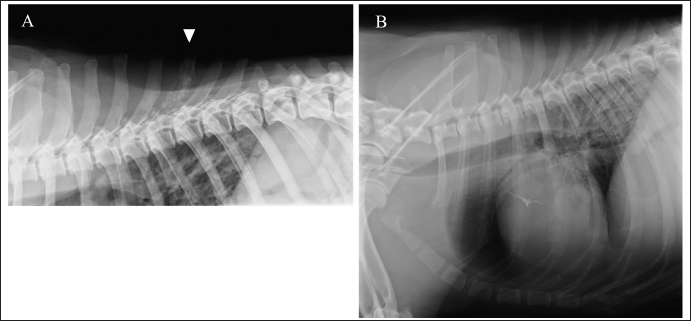

A complete blood cell count revealed neutrophilia with left shift (304.3 × 102/μl; reference range: 19.25–146.25 × 102 /μl) and monocytosis (47.4 × 102/μl; reference range: 3.0–10.0 × 102/μl). The chemistry profile detected high creatine phosphokinase (263 IU/l; reference range: 49–166 IU/l) and high C-reactive protein (2.9 mg/dl; reference range: <1.0 mg/dl). Other comprehensive metabolic panels showed normal results. Thoracic radiographs detected bone lysis of the T7 spinous process and an approximately 1 cm high signal-intensity ring-shaped lesion in the lung (Fig. 1A and B). Urinalysis and fecal examination did not reveal any significant changes. Differential diagnoses included inflammation caused by systemic mycosis and/or bacterial infection and neoplasia.

Fig. 1. Right lateral thoracic radiograph. Bone lysis of T7 spinous process (A). Approximately 1-cm high signal-intensity ring-shaped lesion in the lung (B).